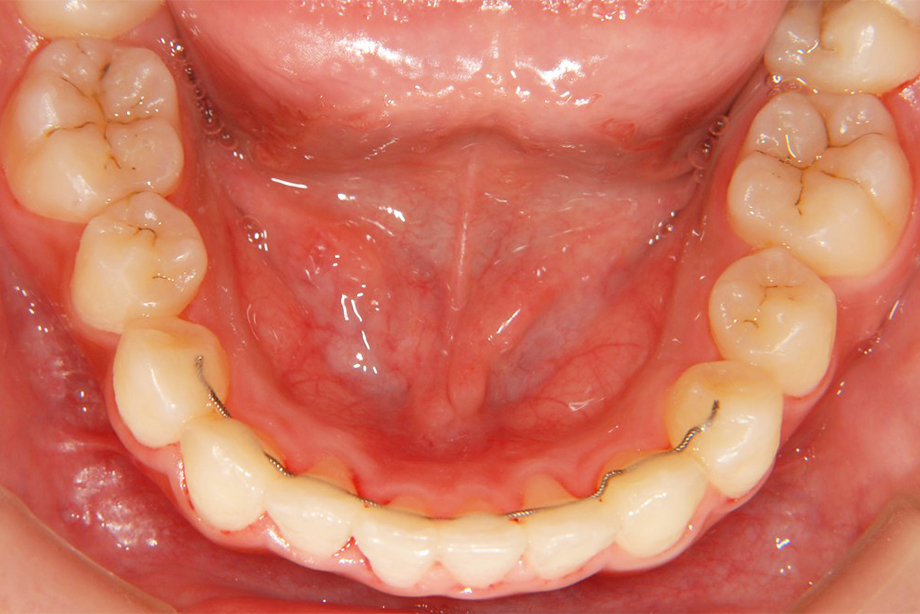

第Ⅰ期治療

乳歯、もしくは乳歯と永久歯が混ざっている時期の治療です。歯の治療というよりも、顎の骨の成長を促したり、歯並びに影響を与える筋機能の訓練などを行います。

- 矯正後

矯正治療は歯に力を加えることにより、顎の骨の中を歯が動くという性質を利用して行う治療です。治療後も、元あった位置に歯が戻ろうとする「後戻り」の可能性があります。

また、頻繁な頬杖や唇を噛みしめる癖や、うつ伏せ寝などによって力が加わり、歯が動いてしまうことがあります。(矯正治療をされない方でも歯並びが少しずつずれてしまうことがあります)

大人になってもきれいな歯並びを維持するためには、癖や生活習慣の改善、毎日の歯みがきはもちろんのこと、定期的なメンテナンスを受けていただくことをおすすめします。(年間に少なくとも2~4回程度が目安です)